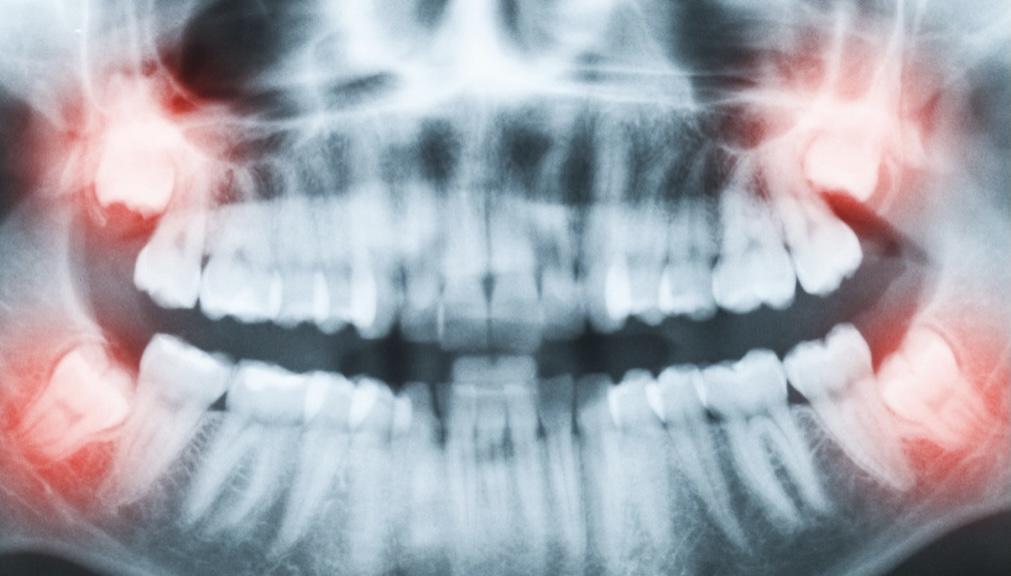

假如吃了止痛藥還是果不,甚至出現(xiàn)了拔牙一側(cè)頭疼,那么有可能出現(xiàn)了干槽癥,應(yīng)該及時找醫(yī)生進行復(fù)診。

(面部腫脹、疼痛嚴重者隨時復(fù)診)